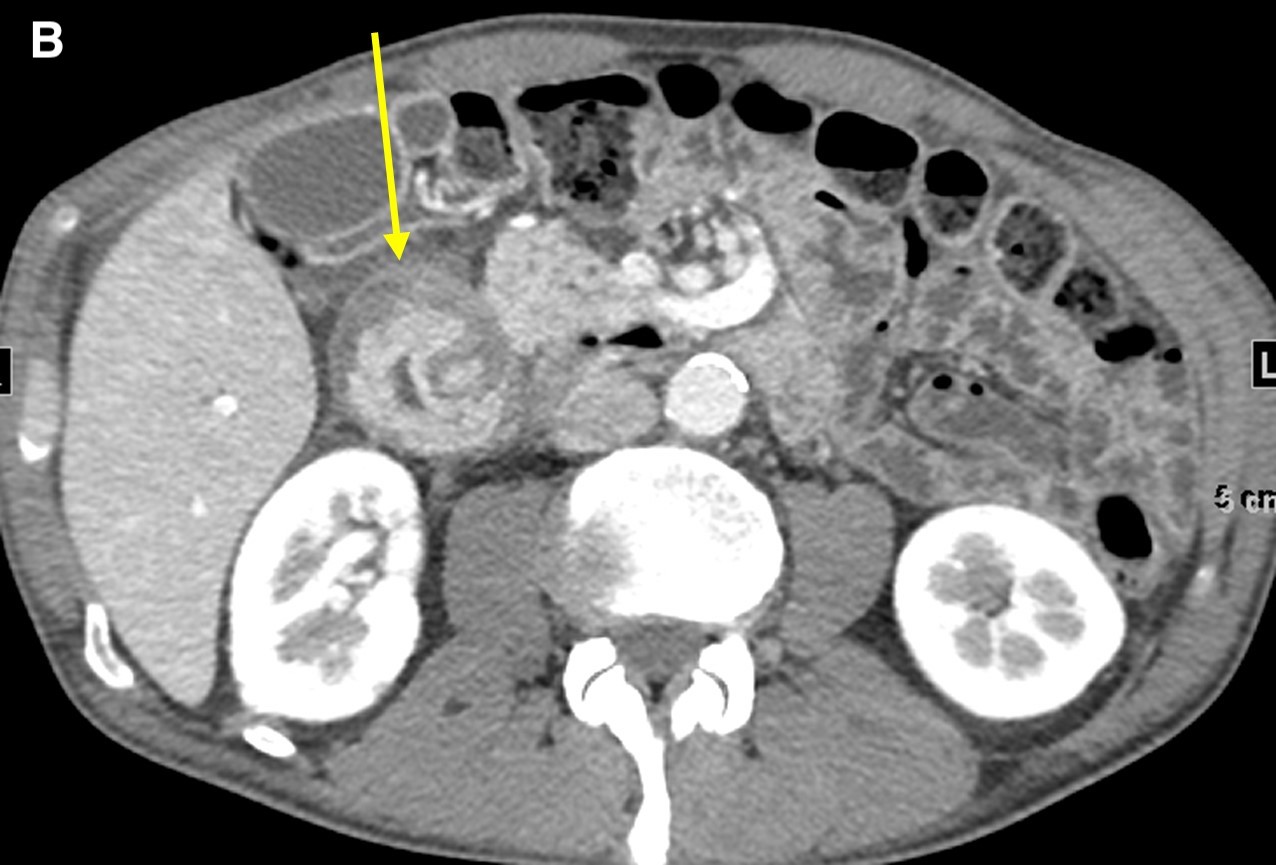

On computed tomography (CT) scans, groove pancreatitis demonstrates crescentic, ill-defined mass formation between the head of the pancreas and duodenum.1 It also shows an abnormal fat-plane between the two.1 This area of fibrotic change shows early isodensity, with late enhancement.1 Duodenal wall thickening is seen, sometimes with cysts or cystic masses within the walls, or the fibrotic tissue within the groove space.1 This cystic degeneration is highly specific to groove pancreatitis, with some studies citing 85.7% to 87.2% of cases with cystic components.1,5 This corresponds to an approximate 92.2% negative predictive value.1 Some nonspecific features include common bile duct (50%) and/or pancreatic duct dilation caused by mass effect of the edematous ampullary tissue/groove soft tissue.3 Our patient presented with diffuse wall thickening of the duodenum, although no cysts were readily identified on CT scans (Figure 2).

Figure 2. Axial images from a contrast-enhanced computed tomography scan demonstrated diffuse wall thickening of the second portion of the duodenum and surrounding inflammation (a and b, arrow) without a discrete periampullary mass. The intact gastroduodenal artery was noted without displacement from the pancreatic head and soft tissue inflammation immediately lateral to it (c, arrow).